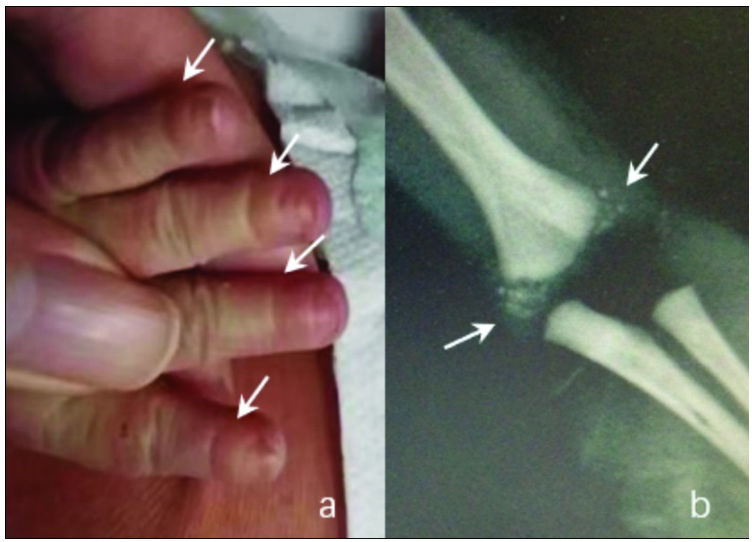

至36周4天,顺产一活男婴,出生体质量3 280 g, Apgar评分:9-9-7。新生儿紫绀,鼻骨低,呼吸不规则,四肢张力低下,手指第一指节均短小,见图2a。X线片显示脊柱两侧、股骨和肱骨干骺端均见多个点状钙化,见图2b。

图2 新生儿点状软骨发育不良的表现。a.新生儿手指第一指节均短小;b.新生儿肱骨干骺端见多个点状钙化。